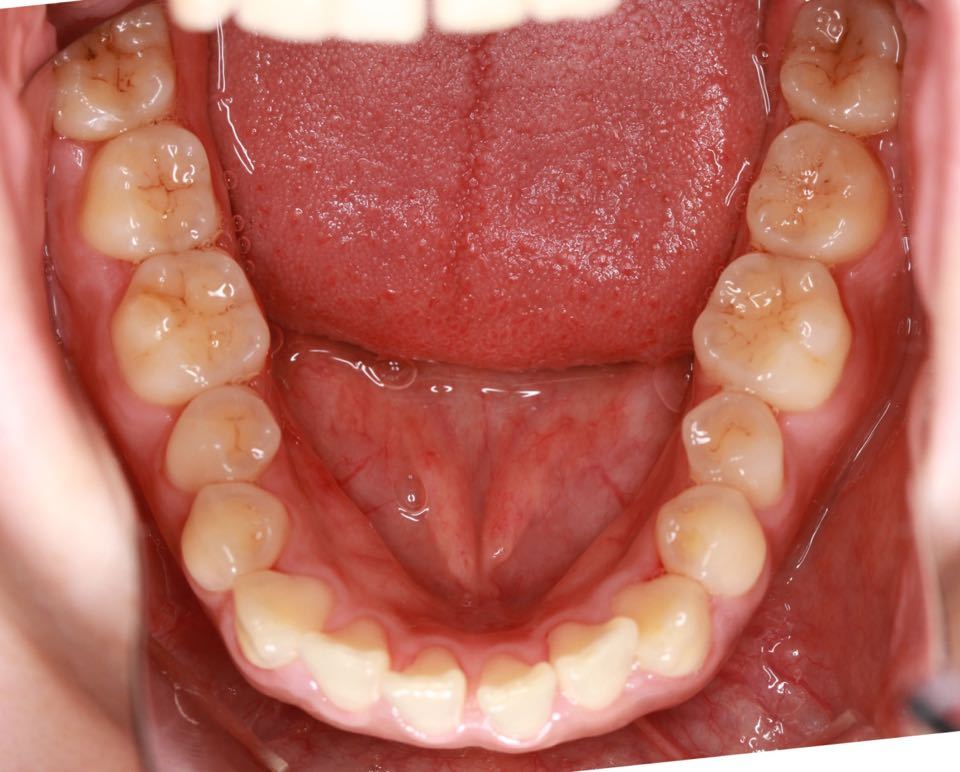

矫正前口内照:

口内:恒牙列,牙列拥挤(中度)。上下颌牙弓呈方圆型。左右对称。右侧磨牙近中性关系,左侧磨牙近中关系,右侧尖牙远中关系,左侧尖牙远牙中性关系。上颌中线偏右2mm,下中性居中。